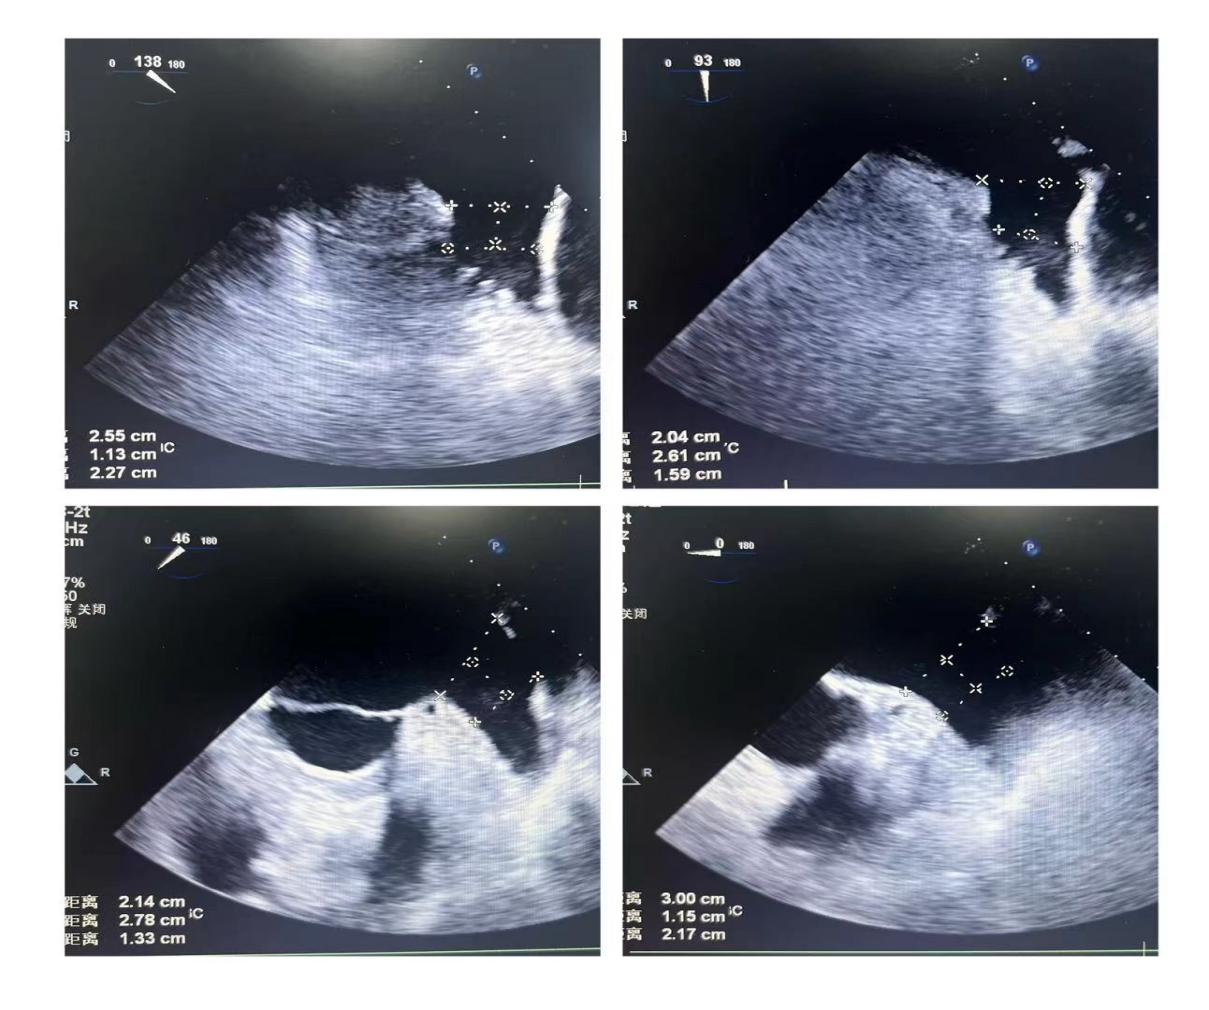

潘教授通过食道超声从4个不同的角度来观察患者左心耳的形态情况,显示心耳为反鸡翅型,位置较低,锚定区为23mm,封堵区为26mm。术者结合多年的临床经验,最终选用型号为LT-LAA-2632的LAmbre™左心耳封堵器对患者进行封堵。

▲(图:通过超声观察进行穿刺)

在食道超声引导下进行房间隔穿刺,由于心耳为反鸡翅型,穿刺位点需靠下靠前,潘教授先在90度双腔切面将定位靠下,再在45度主动脉短轴切面将定位靠前。穿刺成功后上导丝交换九州ku酷游LAnavi™分段控弯导引系统送至心耳口部,经过A、B双弯的调整使得鞘管轴向与心耳同轴,获得理想封堵位置。然后推送钢缆释放出固定盘,锚定后退鞘释放出封堵盘。超声下观察贴合良好,无明显残余分流,牵拉测试稳定,即释放左心耳封堵器。释放后再次通过超声各个角度进行验证,封堵结果完美有效,整个过程一气呵成,手术取得了极大的成功。

牵拉测试稳定 完美有效封堵